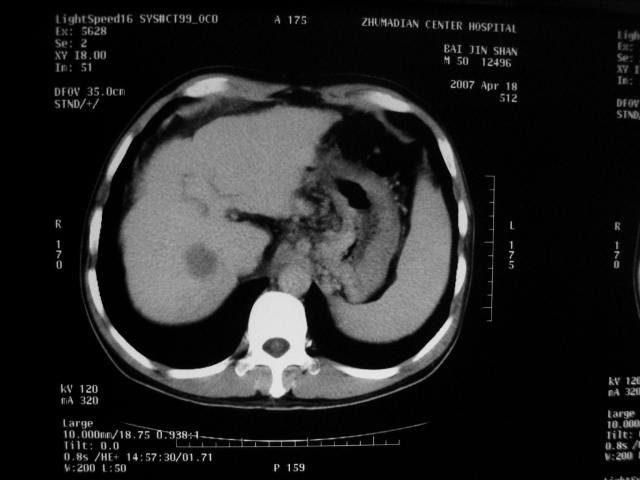

标题: CT7751:病人,50岁,肝硬化多年,行CT三期扫描 [打印本页]

标题: CT7751:病人,50岁,肝硬化多年,行CT三期扫描

动脉期病灶见轻度强化,考虑肝癌可能性大。

动脉期轻度强化 考虑 肝右叶小肝癌可能性大

肝硬化 脾大 胃底静脉曲张 肝癌 门腔间淋巴结肿大

肝硬化、脾大,静脉曲张,肝右叶低密度灶,增强无明显强化,还是考虑肝癌可能性大,建议结合afp检查。

肝癌分为肝细胞性和胆管细胞性,从强化表现来看,确切地说应是胆管细胞癌.